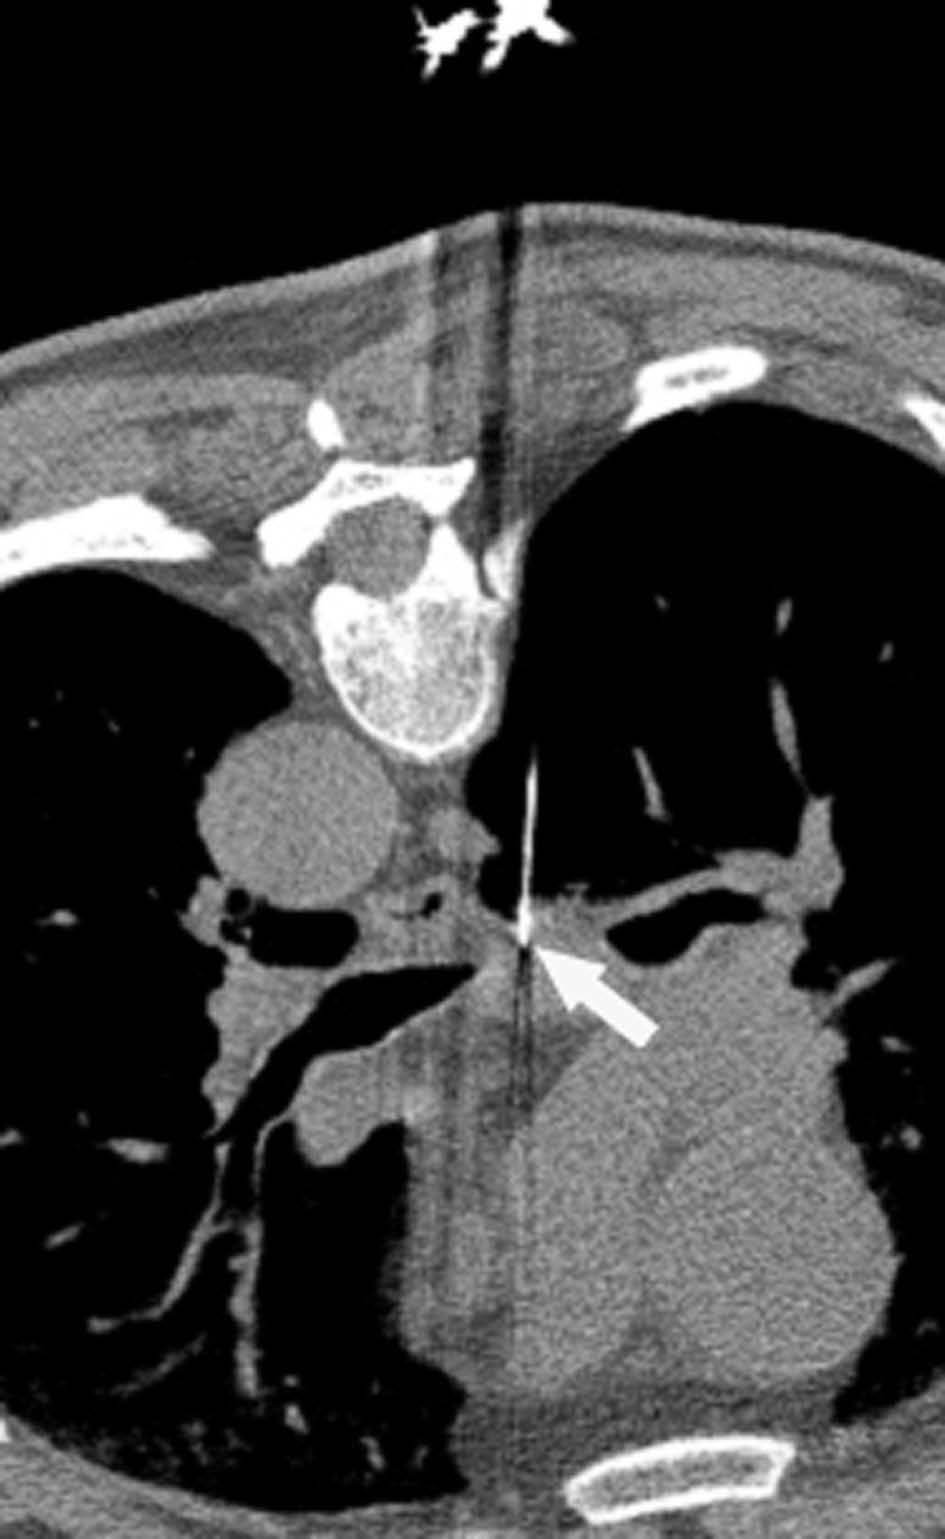

Fig. 4.--Invasión vascular. Tomografía computarizada (TC) torácica con contraste. Corte axial (A) y reconstrucción coronal oblicua (B). Invasión tumoral por continuidad de la vena pulmonar inferior (flecha).